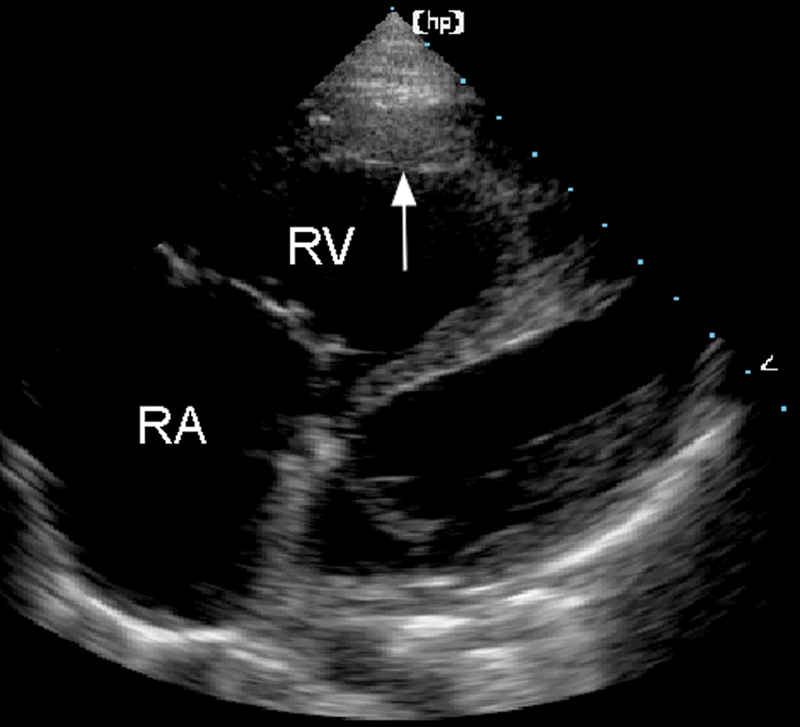

فحوصات تشخيصية لبعض امراض القلب والشرايين التاجية